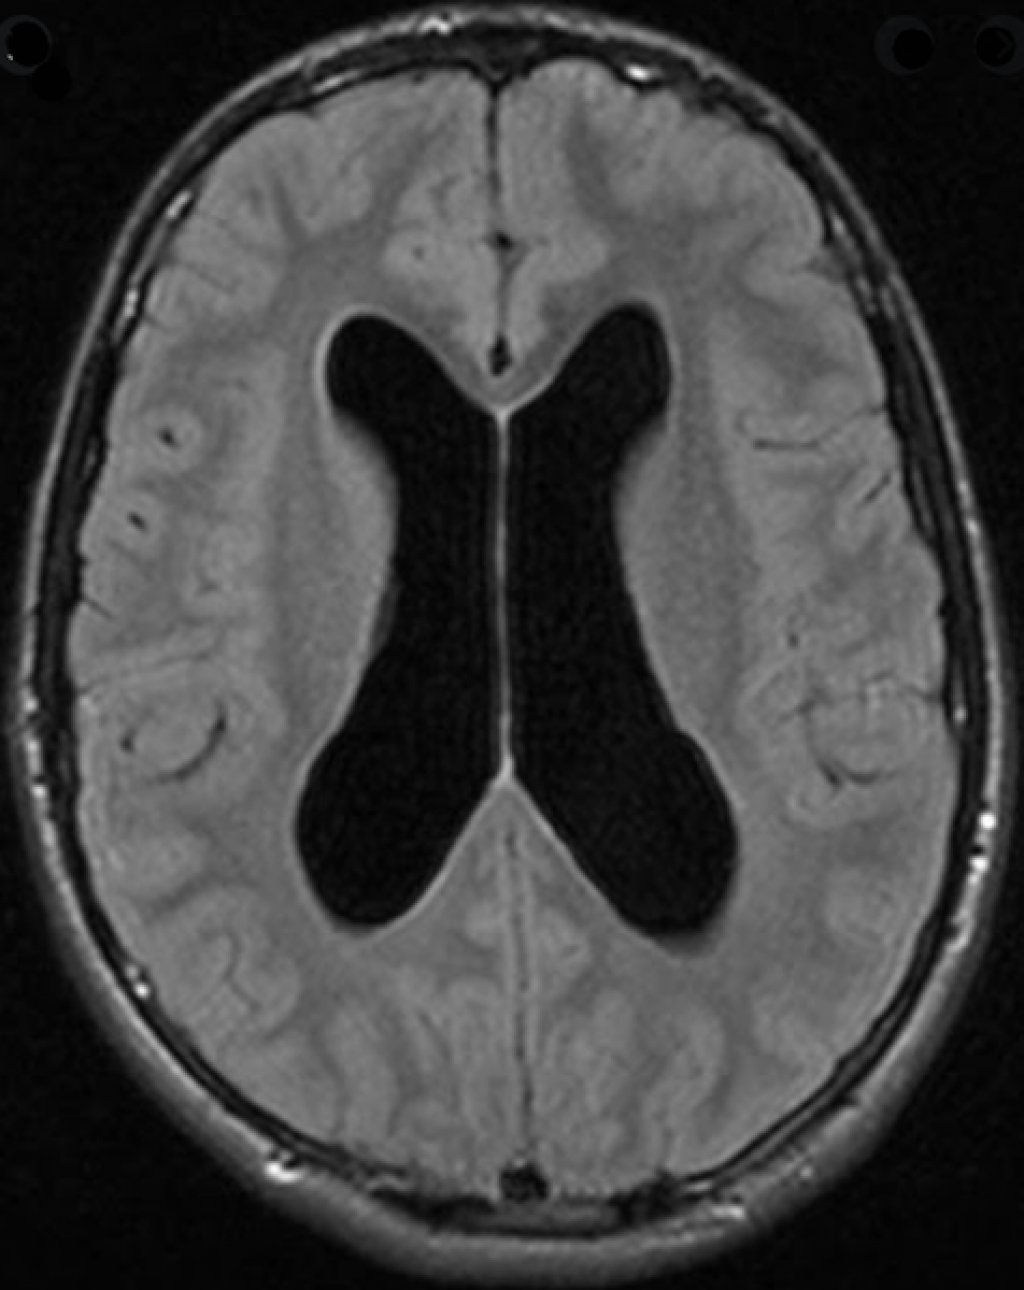

Признаки умеренно выраженной наружная

Признаки умеренно выраженной наружная 113 фото